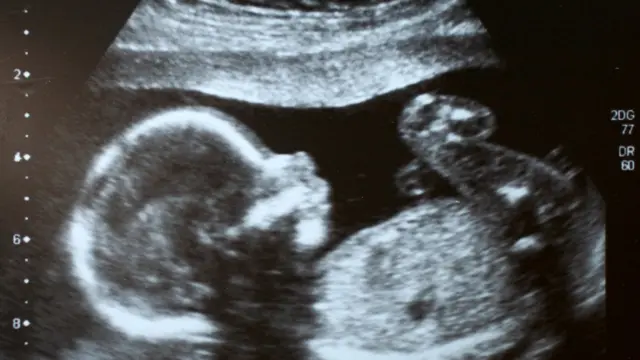

La terrible noticia llegó con la primera ecografía.

Andrea tenía 11 semanas de gestación cuando descubrió que su bebé no tenía ninguna posibilidad de sobrevivir porque tenía un tumor entre el cuello y la cabeza.

Finalmente, el día llegó. La ecografía que le hicieron a las 26 semanas de gestación reveló que la bebé había muerto.